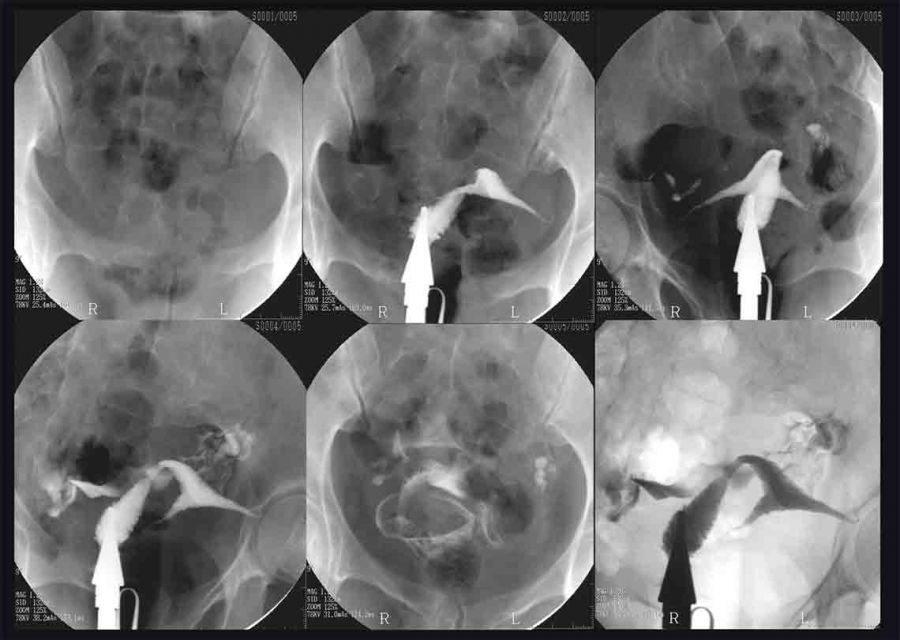

عکس رنگی رحم چیست؟ هیستروسالپنگوگرام (HSG) یک آزمایش اشعه ایکس است. به داخل رحم و لوله های فالوپ و ناحیه اطراف آنها نگاه می کند. در صورتی که برای باردار شدن با مشکل مواجه هستید (ناباروری) ممکن است انجام شود.

انسداد در لوله های فالوپ و یا حفره غیرطبیعی در رحم ممکن است موجب ناباروری زنان شود. مجموعه ای از اشعه ایکس یا فلوروسکوپی رنگ را دنبال می کند که در اشعه ایکس سفید به نظر می رسد، زیرا به داخل رحم و سپس به لوله ها حرکت می کند. در صورت وجود ناهنجاری در شکل رحم مشخص می شود. اگر لوله باز باشد، رنگ به تدریج آن را پر می کند. رنگ به داخل حفره لگن می ریزد، جایی که بدن آن را جذب می کند.

در طول آزمایش، یک رنگ (ماده کنتراست) از طریق یک لوله نازک قرار می گیرد. این لوله از طریق واژن وارد رحم می شود. از آنجایی که رحم و لوله های فالوپ به هم متصل هستند، رنگ به داخل لوله های فالوپ جریان می یابد. تصاویر با استفاده از پرتو ثابت اشعه ایکس (فلوروسکوپی) در حین عبور رنگ از رحم و لوله های فالوپ گرفته می شود.

آزمایش HSG یک عکس برداری با اشعه ایکس از رحم و لوله های فالوپ است که با استفاده از رنگ کنتراست، حفره رحم و لوله های فالوپ را که ساختارهای توخالی با فضاهای بالقوه هستند، متسع می کند. اشعه ایکس معمولی رحم و لولهها را نشان نمیدهد، اما تزریق رنگ به آرامی به داخل حفره، حفره و لولهها را باز میکند و اجازه میدهد تا در عکس رادیوگرافی تصویربرداری شوند. این آزمایش برای تشخیص مسدود شدن کامل یا جزئی لوله های فالوپ استفاده می شود. همچنین نشان می دهد که آیا رحم از نظر اندازه و شکل طبیعی است یا خیر. این شرایط رحم و لوله های فالوپ می تواند بر ناباروری در زنان تأثیر بگذارد.

روش تست HSG

آزمایش HSG در مجموعه رادیولوژی انجام می شود. بیمار بیدار است و در واقع می تواند آزمایش را با متخصص باروری تماشا کند. پزشک یک اسپکولوم را وارد واژن میکند و سپس یک کاتتر کوچک را از طریق دهانه رحم به داخل رحم هدایت میکند. سپس نوعی رنگ موقت به نام محیط کنتراست رادیویی از طریق کاتتر فشار داده می شود تا رحم و لوله ها را پر کند که می توان آنها را روی مانیتور مشاهده کرد. این مایع اندام ها را برجسته می کند تا به وضوح روی صفحه ظاهر شوند.

تصویر به دست آمده شکل و اندازه رحم را نشان می دهد. اگر فیبروم یا پولیپ در حفره رحم وجود داشته باشد، رنگ در اطراف آنها جریان می یابد و بدین ترتیب این انسدادها مشخص می شود. HSG یک تست غربالگری خوب برای ناهنجاری های رحمی از جمله سپتوم رحم، رحم تک شاخ، رحم دو شاخ و رحم دیدلفی است.

اگر رنگ در تمام طول لوله های فالوپ جریان داشته باشد، نشان می دهد که هیچ انسدادی وجود ندارد. با این حال، اگر رنگ در هر نقطه از هر یک از لولهها متوقف شود، پزشک میتواند ببیند که لولهها به طور جزئی یا کامل بسته شدهاند که به آن بیماری لوله گفته میشود. ناباروری می تواند به این دلیل باشد که اسپرم به دلیل انسداد، نمی تواند به تخمک برای لقاح در لوله فالوپ برسد. چنین محدودیتی در لوله همچنین می تواند مانع از سفر تخم بارور شده (جنین) به رحم برای لانه گزینی و بارداری شود.